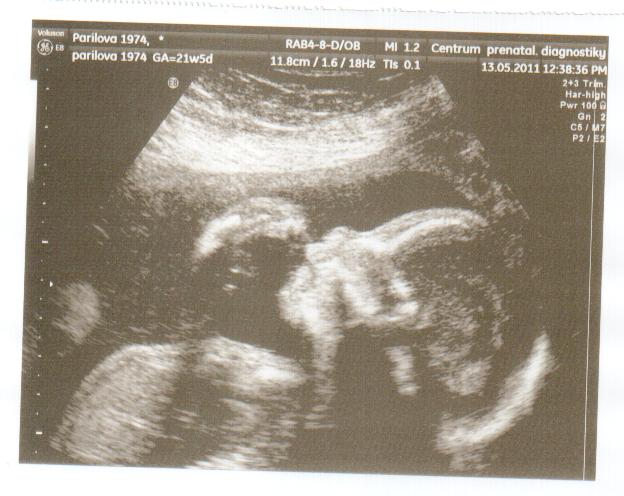

Ahoj holky, zjistila jsem , že v Brně v Heliosu si můžete nechat udělat dvd v 3D jen za 500 kč, obvykle se dělá kolem 20 tt do 26 tt..Jinak posílám vám fotku naši holčičky, co jsme dostali ve čtvrtek..

Marketto první odkaz mi pěkně sekl pc, škoda že jsem se napřed nepodívala dál. Ale mimušek nádhernej. Taky přidám ult. Holky ten můj malej má přední ret dopředu, napřed jsem se lekla jestli nebude mít nějaký předkus nebo něco ale pak jsem si vzpoměla že to doktorka pořizovala zrovna když polykal, tak snad to je jen takový záběr. kamarádka mě pak uklidnila že tak jsou všechny miminka ale Markett to tak na ult nemá. No ale budu se uklidňovat tím polykáním.

Je moc pěkný Pavlo, sedím ted s manželem u pc, tak se nám oběma líbí moc. Ta naše bude asi mít pusinku po tatínkovi, má výrazné rty..Kéž by, to tak bylo!